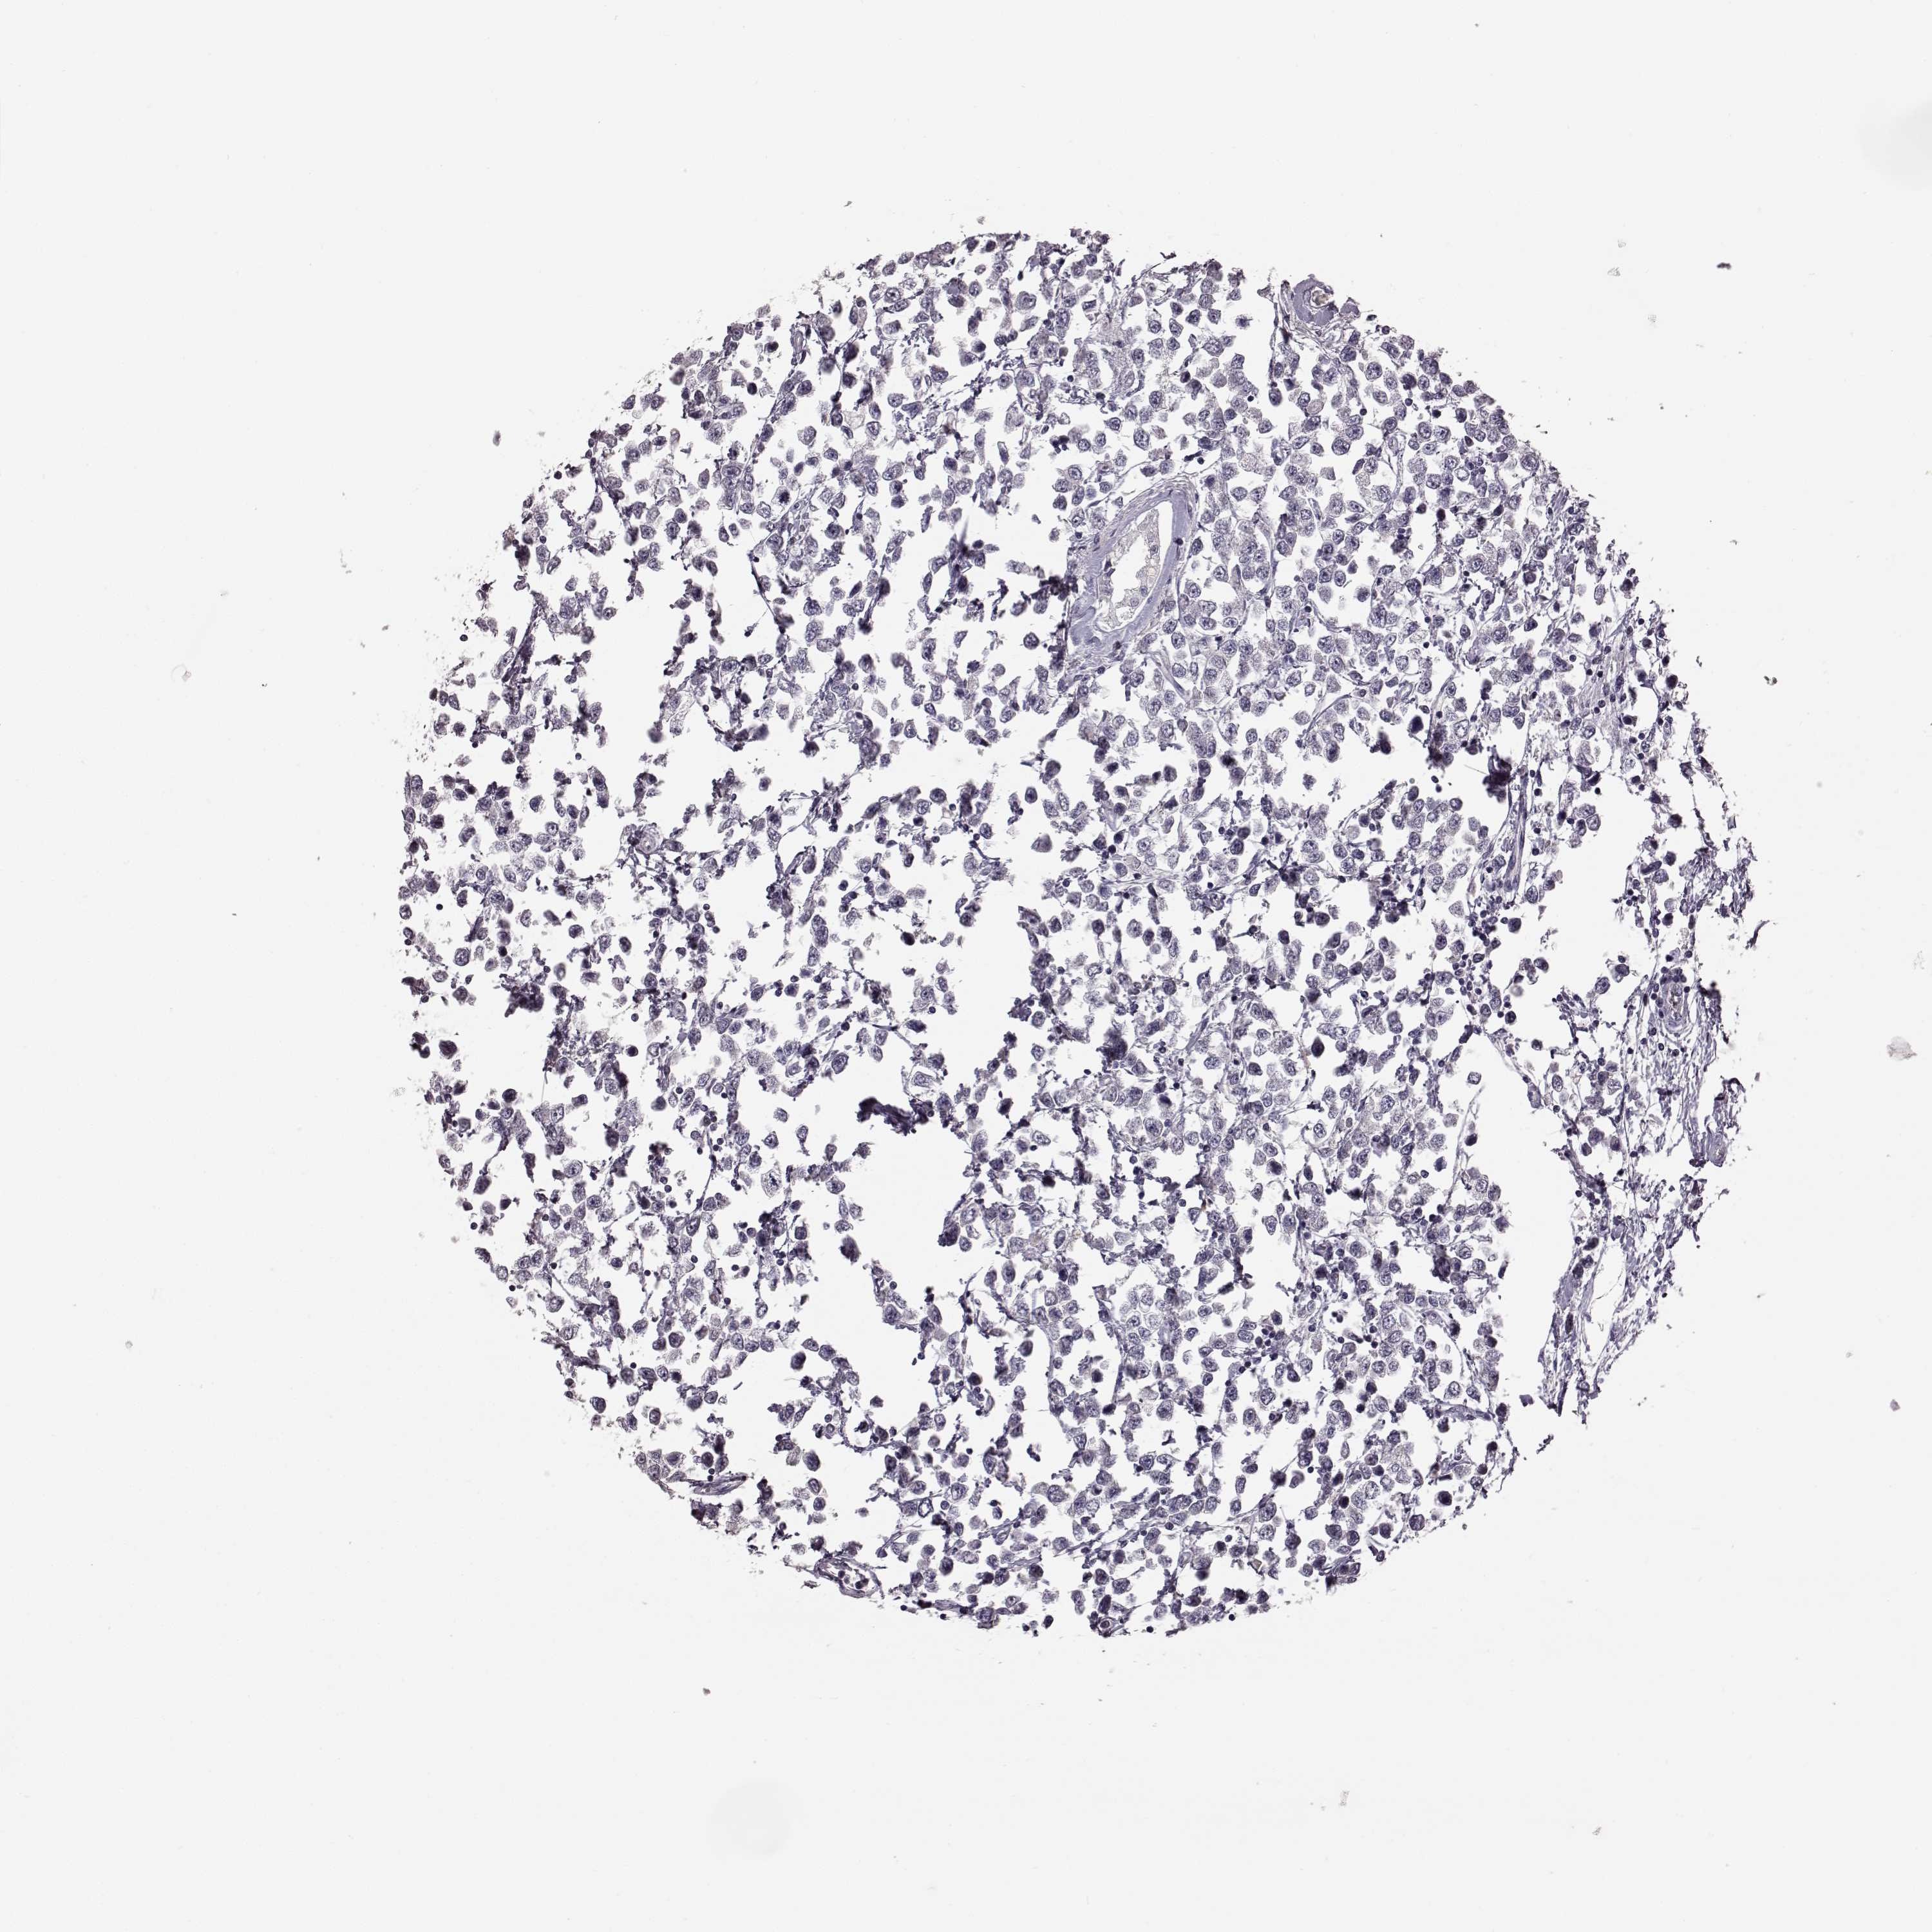

TESTIS CANCER - Protein expressioni

A mouse-over function shows sample information and annotation data. Click on an image to view it in a full screen mode. Samples can be filtered based on level of antibody staining by selecting one or several of the following categories: high, medium, low and not detected. The assay and annotation is described here.

Note that samples used for immunohistochemistry by the Human Protein Atlas do not correspond to samples in the TCGA dataset.

Antibody stainingi

Antibody staining in the annotated cell types in the current human tissue is reported as not detected, low, medium, or high, based on conventional immunohistochemistry profiling in selected tissues. This score is based on the combination of the staining intensity and fraction of stained cells.

Each image is clickable and will lead to virtual microscopy that enables deeper exploration of all samples and also displays staining intensity scores, fraction scores and subcellular localization as well as patient and tissue information for each sample.

Antibody HPA042369

Staining

High

Medium

Low

Not detected

Intensity

Strong

Moderate

Weak

Negative

Quantity

>75%

75%-25%

<25%

None

Location

Nuclear

Cytoplasmic/membranous

Cytoplasmic/membranous,nuclear

Seminoma, NOS

Carcinoma, Embryonal, NOS

Teratoma, malignant, NOS